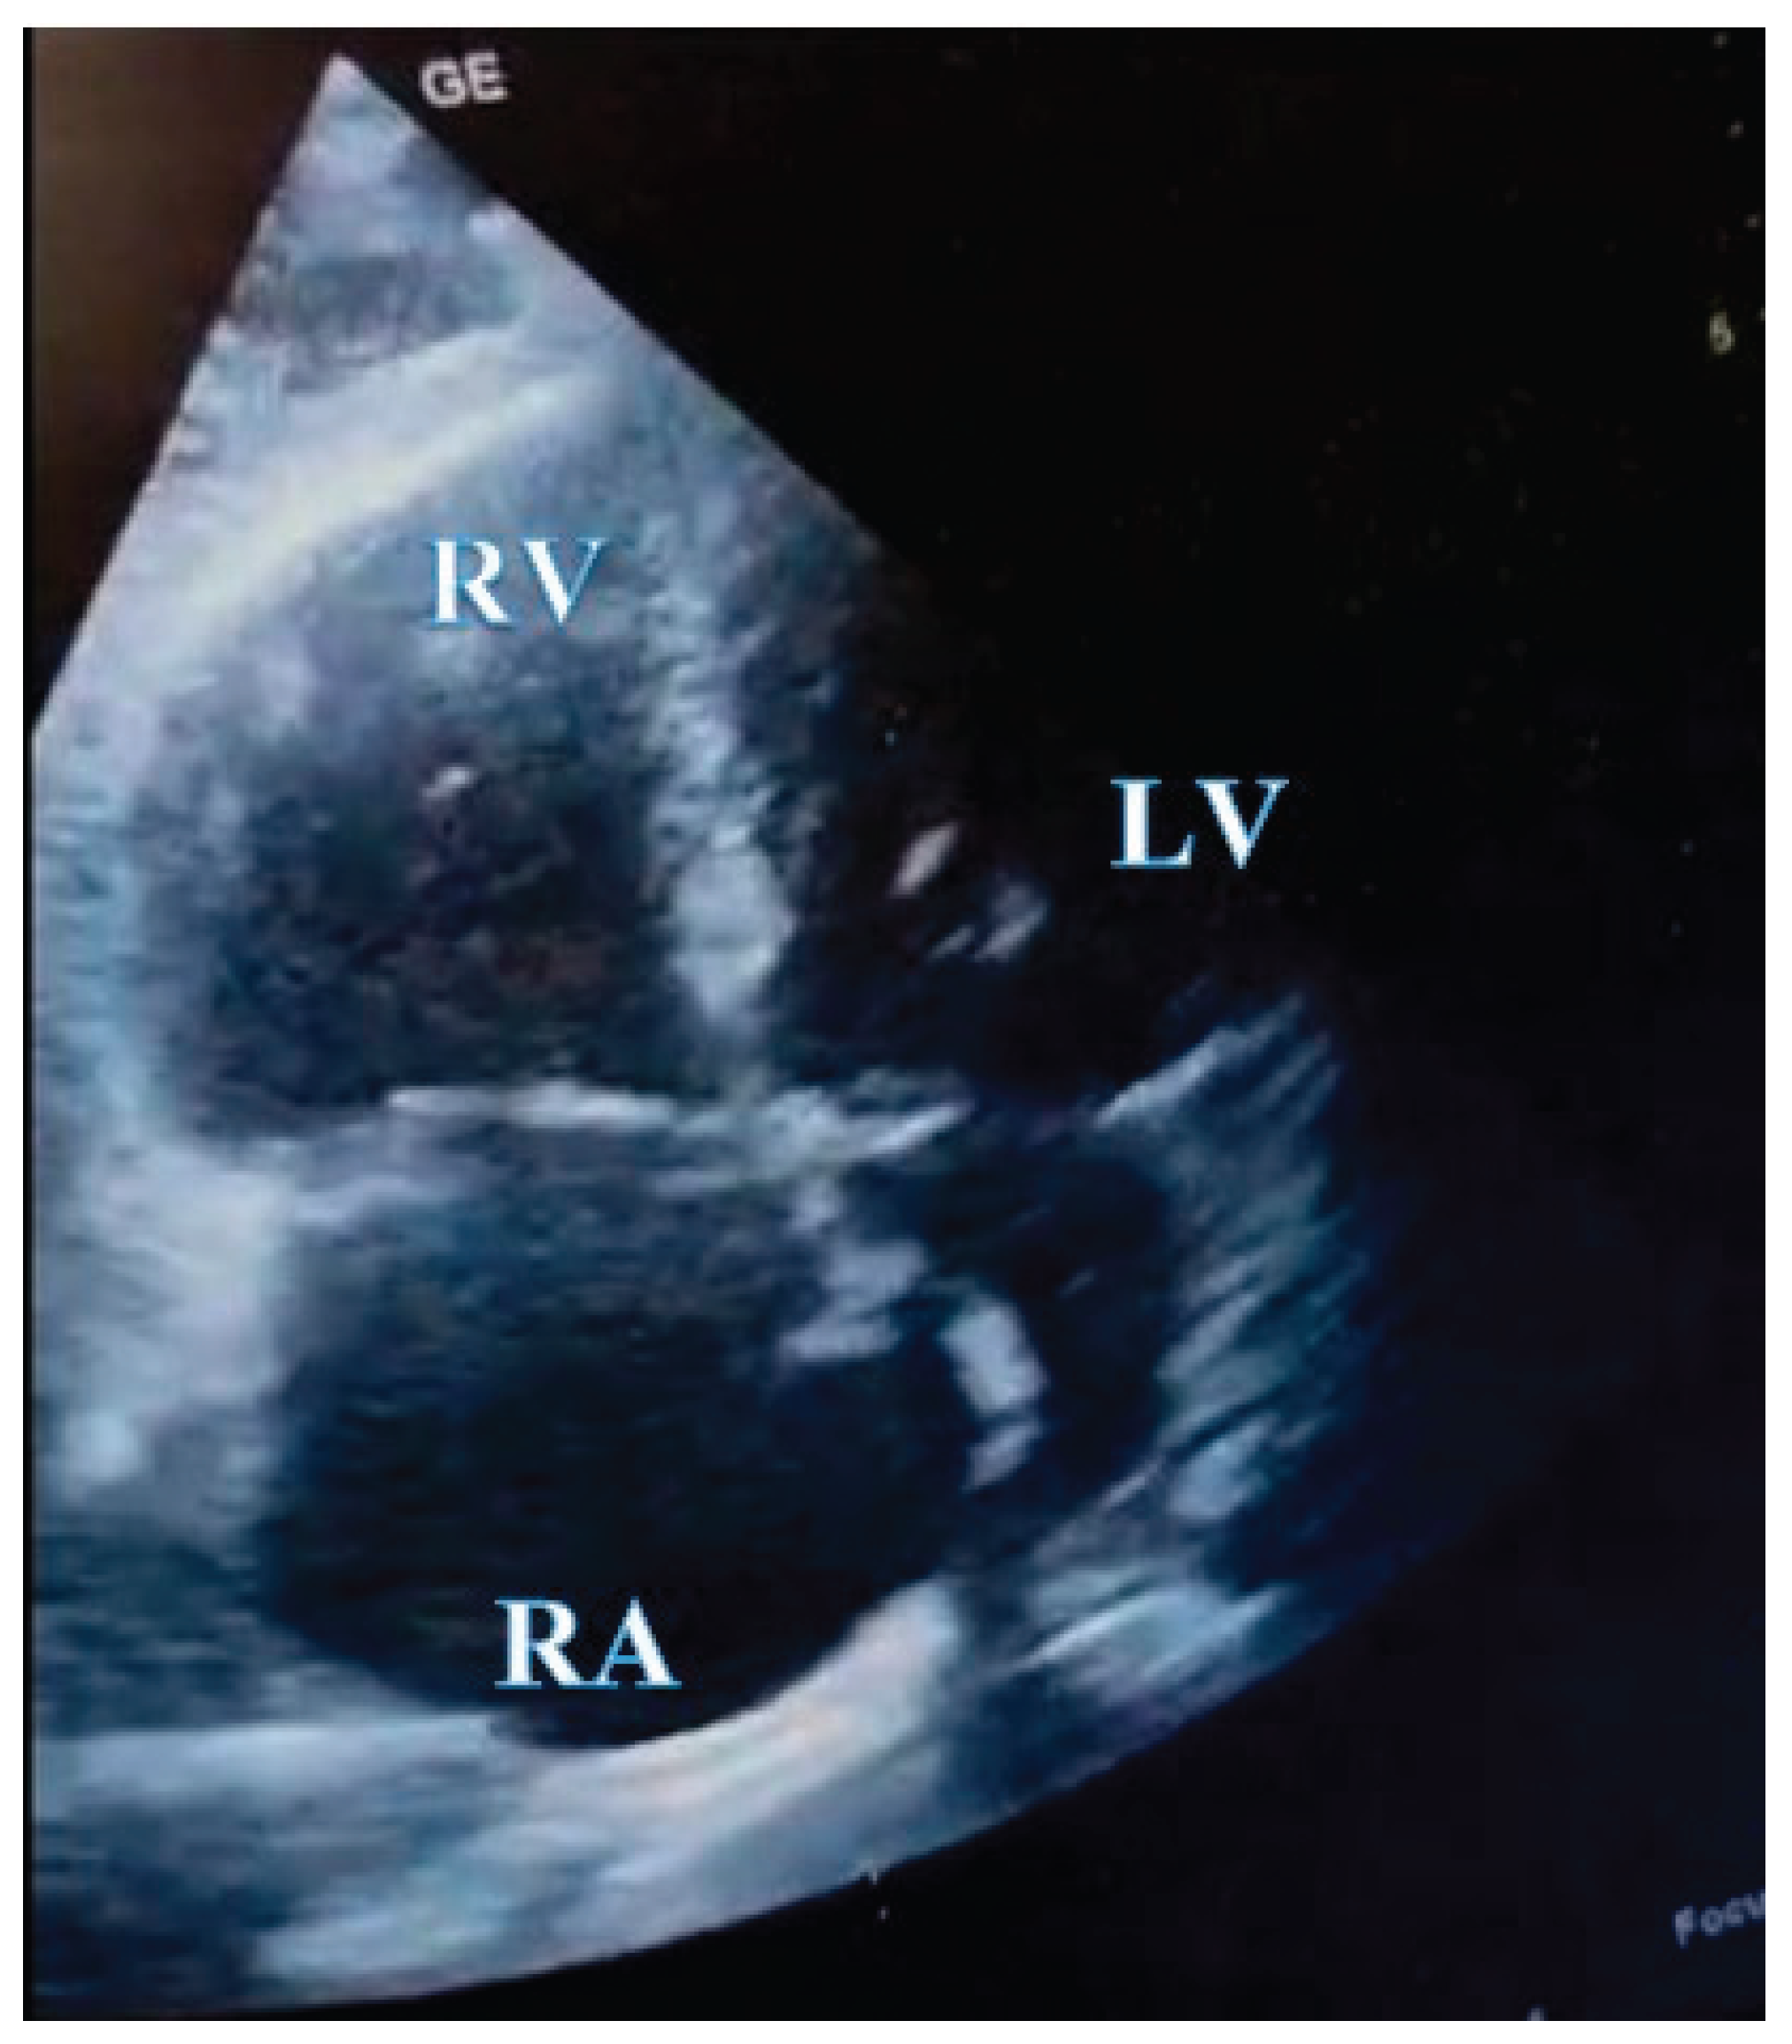

In the absence of any anamnestic or clinical evidence suggestive of pulmonary or myocardial infection (rapid influenza A/B and COVID-19 tests were also negative), acute myocardial infarction, or aortic dissection, and considering the laboratory findings, the clinical suspicion of pulmonary embolism became increasingly prominent, prompting the immediate performance of transthoracic echocardiography. Point-of-care transthoracic echocardiography (POCUS-TTE) confirmed the physiological impact of acute right ventricular strain (Figure 1A and Figure 1B), demonstrating severe right ventricular dilation (46 mm below the tricuspid annulus), markedly reduced systolic function (tricuspid annular plane systolic excursion, TAPSE = 12 mm), and paradoxical interventricular septal motion resulting in a “D-shaped” left ventricle - findings consistent with acute right ventricular pressure overload (RV/RA gradient = 40 mmHg) (Figure 2). Crucially, a large, highly mobile, serpentine thrombus was visualized within the right atrium, with its free-floating end prolapsing toward the tricuspid valve orifice. The concomitant presence of asymptomatic left popliteal deep vein thrombosis (DVT) was also documented, with the thrombus exhibiting a non-adherent proximal end and an unstable, mobile pattern, further supporting the diagnosis of massive pulmonary embolism.

Figure 2. POCUS -TTE pre-thrombolysis shwoing a thrombus in transit. Apical four-chamber view from transthoracic echocardiography showing a large, serpentine, free-floating thrombus (arrowhead) within the right atrium, seen prolapsing toward the tricuspid valve. Right ventricular cavity is larger than the left ventricular cavity RV/LV>1.